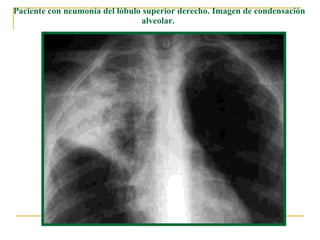

Paciente con neumonía del lóbulo superior derecho. Imagen de condensación alveolar.

Detalle de radiografía posteroanterior en un paciente con neumonía del lóbulo superior derecho. Imagen de condensación alveolar.